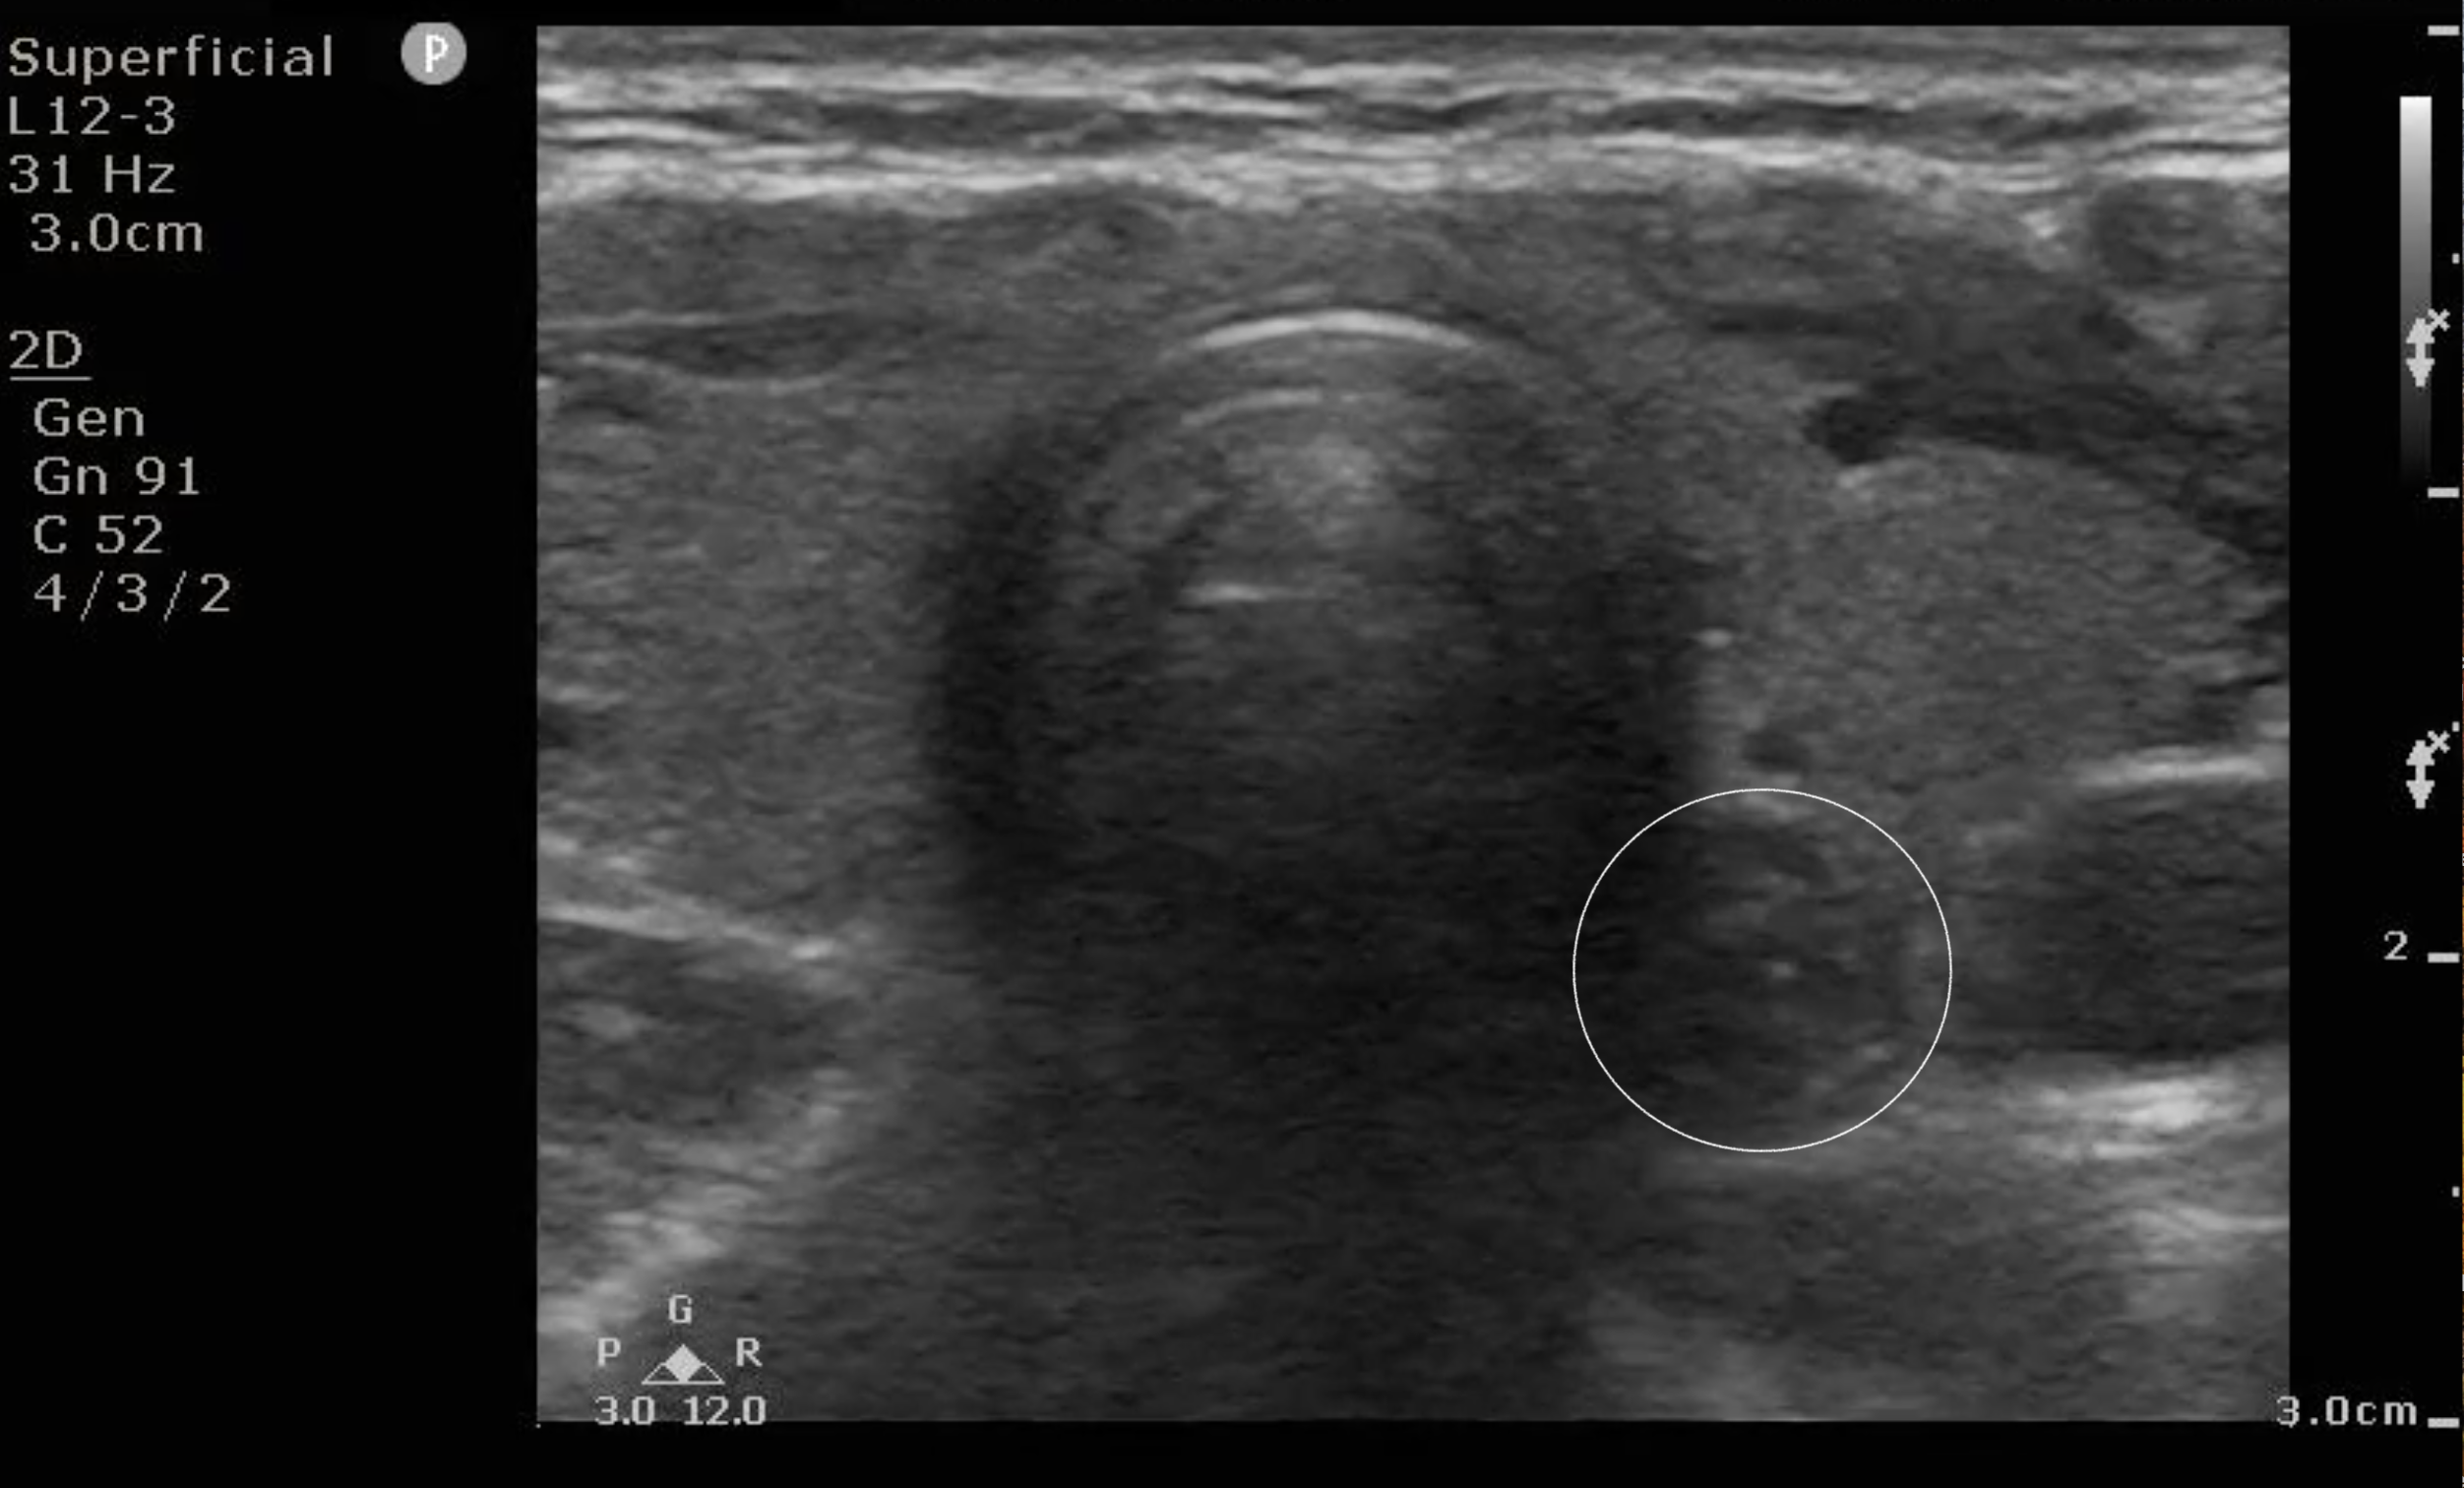

- Figure 7a and b. Step 7: Just caudal to the cricoid cartilage, you will start to see trachea with its intermittent tracheal rings. To the left of the patient’s trachea, you will frequently see the esophagus with a bull’s eye appearance (circle).